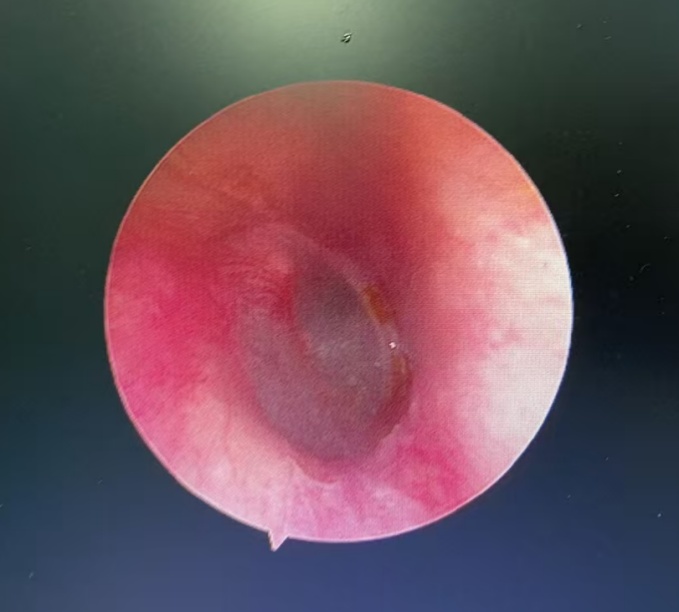

经急诊转诊到耳鼻咽喉头颈外科,医生用电耳镜进行观察,发现一只蟑螂卡在外耳道深处。金先生一直喊疼,并说感觉到耳道内物体的活动。“别怕,我先用石蜡油把虫子杀死,虫子有点深,晚点再通过耳内镜帮你取出来。”医生一边操作一边安抚金先生。

不久后,确认蟑螂已被“处死”,金先生疼痛暂时缓解,大清早又赶紧去做耳内镜,医生最终用镊子从金先生外耳道取出了指甲盖大小的蟑螂,并为他进行耳道消毒。